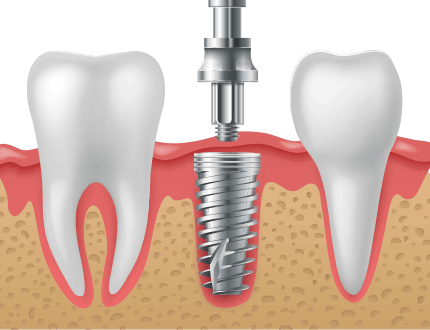

발치즉시 임플란트는 말그대로 보존이 불가능한 치아를 발치하자 마자 치아를 발치한 곳에 임플란트를 식립하는 술식을 말합니다.

발치 즉시 임플란트는 문제치아를 발치한 당일 바로 임플란트를 식립함으로써 여러 번의 시술, 마취에 대한 부담감이 적고

치료기간을 단축할 수 있는 고난이도 시술법입니다.

시술의 단계를

줄일 수 있어 치료기간을

단축시킵니다.

회복시간과 치료기간이

단축되어 빠른 일상생활

복귀가 가능합니다.